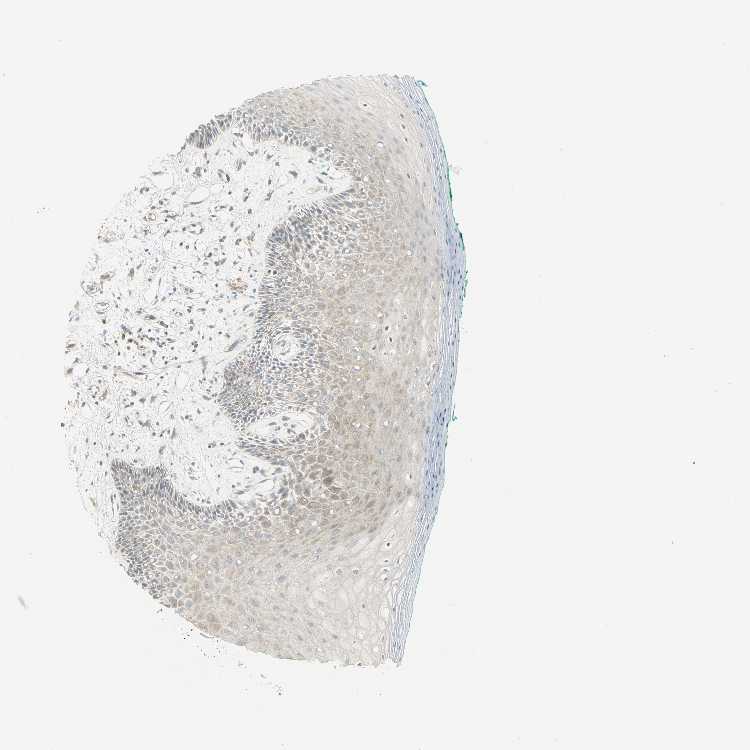

TISSUE PRIMARY DATA ORAL MUCOSA Show tissue menu

ORAL MUCOSA - Antibody stainingi

Antibody staining in the annotated cell types in the current human tissue is reported as not detected, low, medium, or high, based on conventional immunohistochemistry profiling in selected tissues. This score is based on the combination of the staining intensity and fraction of stained cells.

Each image is clickable and will lead to virtual microscopy that enables deeper exploration of all samples and also displays staining intensity scores, fraction scores and subcellular localization as well as patient and tissue information for each sample.

Antibody HPA041785Antibody HPA069311Antibody CAB005580

Squamous epithelial cells LowMediumLow